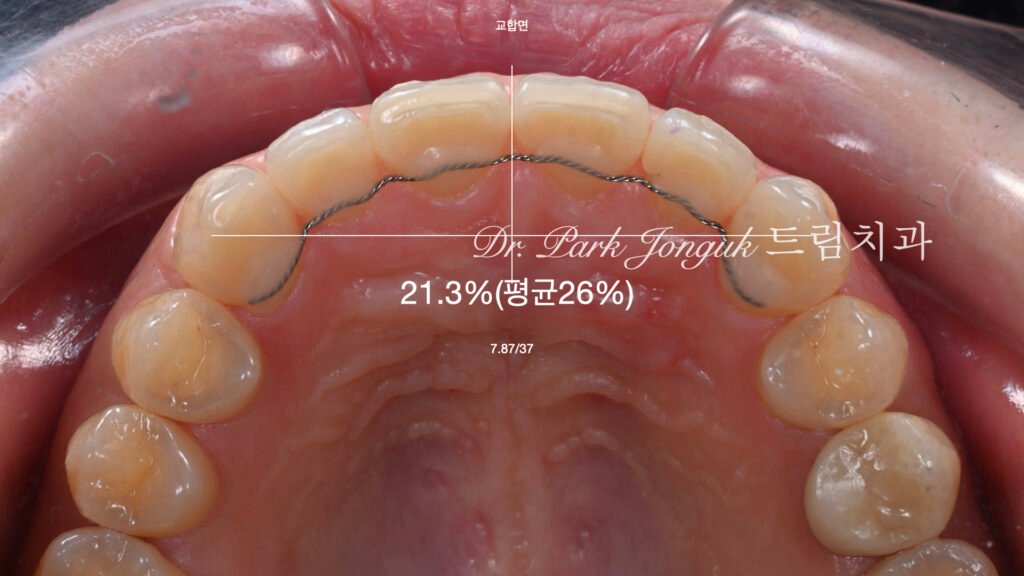

사진 1. 교정 후 내원한 상태

기능적 문제는 없지만 치아 배열이 평평하고 입체감이 부족해 심미적으로 아쉬움이 남음.

사진 2~5. 왁스업(Wax-up) 정밀진단

교정 후 악궁이 납작해진 형태를 보정하기 위해 치아 비율과 곡선을 재설계.

얼굴형, 미소선, 치아 크기를 분석하여 이상적인 조화를 계획.